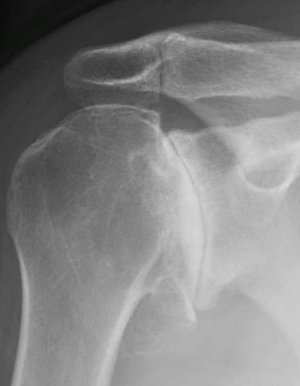

View On GoogleThe Risk of Shoulder Osteoarthritis Should Not Be Discounted Either...

Anatomic Shoulder Replacement

Anatomic Shoulder Replacement replaces part of the joint with safe, biocompatible materials that ensure smooth, continuous movement. Anatomic Replacement is named because the humeral head, or ball, is replaced with a ball. The glenoid, or socket, is replaced with a socket shaped prosthesis. In this replacement, like replaces like.

Reverse Shoulder Replacement

Your surgeon may recommend a reverse shoulder replacement. This surgery utilizes a joint implant device that alters the natural movement of the shoulder joint, restoring function and relieving symptoms. This type of replacement may be useful in severe rotator cuff disease, some complex fractures of the shoulder, as well as some arthritis patterns where to glenoid, or socket, will not accommodate a traditional socket replacement.

Reverse shoulder replacement reverses the anatomy, and the ball is replaced with a socket, likewise; the socket is replaced with a ball (glenosphere).